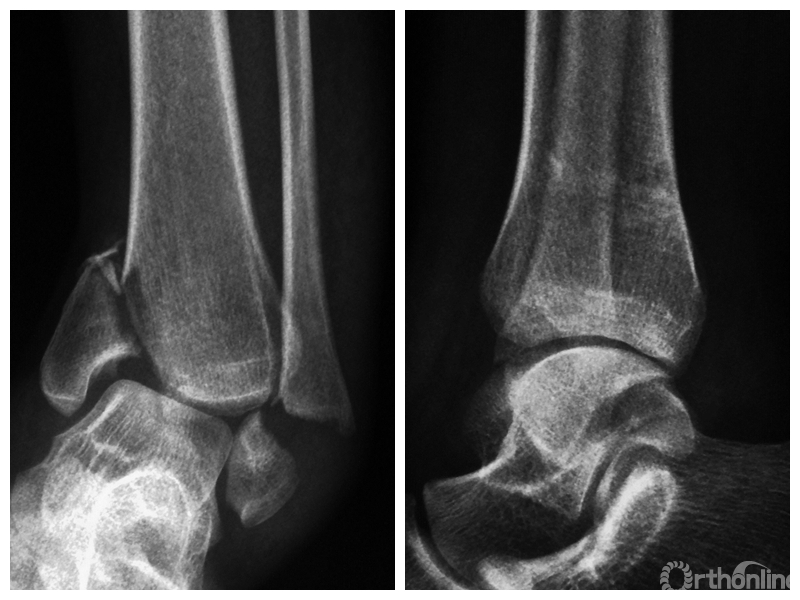

图1 支撑钢板固定组患者,女,63岁,右侧旋后-内收型II度踝关节骨折 a. 术前正侧位X线片;b. 术前CT;c. 术后2周正侧位X线片;d. 术后2年正侧位X线片

图1a 术前正侧位X线片

两组患者均获随访,支撑钢板固定组随访时间46~91,平均64.5个月;螺钉固定组随访时间44~86,平均59.5个月。支撑钢板固定组患者术后完全负重时间为(11.5±1.6)周,较螺钉固定组的(12.6±2.3)周显著缩短,比较差异有统计学意义(t=2.05,P=0.04)。X线片复查示,支撑钢板组均获解剖复位,均达愈合;螺钉固定组有20例获解剖复位,2例畸形愈合,1例不愈合,支撑钢板组骨折愈合时间为(11.5±1.6)周,螺钉固定组为(12.0±1.7)周,比较差异无统计学意义(t=1.06,P=0.30)。见图1、2。支撑钢板固定组3例(10%)、螺钉固定组4例(17.4%)发生创伤性关节炎,均采取保守治疗;两组比较差异无统计学意义(P=0.45)。